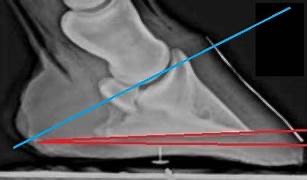

L’angle que la troisième phalange P3 doit faire avec le sol est un indicateur de la santé et de la performance locomotrice du cheval. On parle généralement d’angle palmaire (pour les antérieurs) ou plantaire (pour les postérieurs). C’est angle est idéal entre +3° et +7°. P3 apparait donc sur une vue radio, avec la pointe plus basse que les processus palmaires.

Ce qui impacte directement le placement de P3 et les efforts engendrés sur l’os naviculaire, va être la longueur de la pince du cheval et la hauteur des talons. L’état de santé de la fourchette et de la lacune centrale, ainsi que l’état de développement des cartilages ungulaires vont être des éléments tout aussi déterminants. Les chevaux présentant des aplombs avec des paturons bas jointés sont aussi plus sujets aux problèmes de naviculaire.